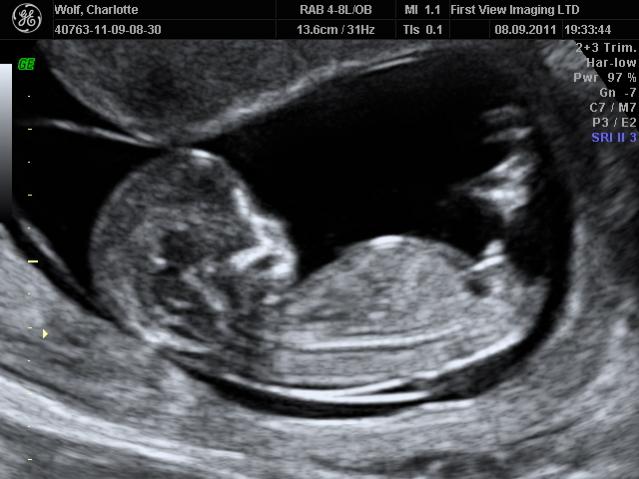

Why are boy nubs all so different from each other?

Hey ladies! Just pondering nubs until my anatomy scan. After seeing so many nubs on the internet, I'm wondering, why do boy nubs differ so much? Girls tend to be all similar: close to the bottom, straight out, some with a fork.

But boys: some are little stacked blobs, some are long straight lines with a bump at the end, some look like hockey sticks or pipes, some stick straight up and some are pretty close to parallel. What the heck? I thought girls were supposed to have the complicated anatomy! Haha.

But here are some examples of what I mean with the different "types":